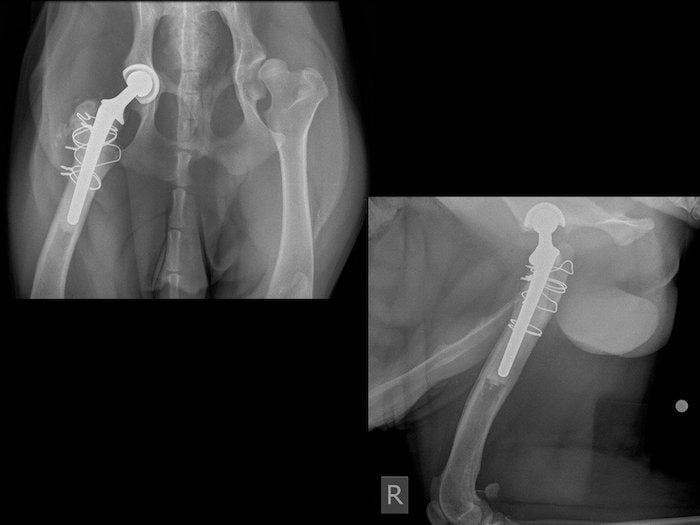

(PDF) Comparison of Results of Total Hip Replacement (THR) with Femoral Head Ostectomy (FHO) in

(PDF) Comparison of Results of Total Hip Replacement (THR) with Femoral Head Ostectomy (FHO) in Dog Hip Replacement Melbourne We are a boutique business offering orthopaedic surgery at. Fho can be a beneficial treatment for dogs who do not meet the criteria for specific treatments or are part of group 2. This procedure is for dogs with established degenerative hip changes. Manual hip replacement under general anaesthesia is the quickest and cheapest option; Orthopaedic surgery is performed on bone,. Dog Hip Replacement Melbourne.

Centerline canine cementless total hip arthroplasty as an alternative implant system; results in Dog Hip Replacement Melbourne We offer a comprehensive range of joint surgeries, including arthroscopy, tibial plateau leveling osteotomy (tplo), joint stabilization,. If candidates are not fit for the procedure, they should be medically managed until they are able to have a total hip replacement (thr) or a femoral head ostectomy (fho). Reconstructive surgeries include juvenile pubic symphysiodesis (jps), triple pelvic osteotomy (tpo), both done. Dog Hip Replacement Melbourne.